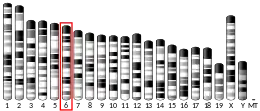

Alpha-synuclein (aSyn) is a protein that, in humans, is encoded by the SNCA gene.[5] Alpha-synuclein is a neuronal protein that regulates synaptic vesicle trafficking and subsequent neurotransmitter release.[6][7]

Familial Parkinson's disease is associated with mutations in the -synuclein (SNCA) gene. In the process of seeded nucleation, alpha-synuclein acquires a cross-sheet structure similar to other amyloids.[12]

In rare cases of familial forms of Parkinson's disease, there is a mutation in the gene coding for alpha-synuclein. Five point mutations have been identified thus far: A53T,[110] A30P,[111] E46K,[112] H50Q,[113] and G51D;[114] however, in total, nineteen mutations in the SNCA gene have been associated with parkinsonism: A18T, A29S, A53E, A53V, E57A, V15A, T72M, L8I, V15D, M127I, P117S, M5T, G93A, E83Q, and A30G.[115]

It has been reported that some mutations influence the initiation and amplification steps of the aggregation process.[116][117] Genomic duplication and triplication of the gene appear to be a rare cause of Parkinson's disease in other lineages, although more common than point mutations.[118][119] Hence certain mutations of alpha-synuclein may cause it to form amyloid-like fibrils that contribute to Parkinson's disease. Over-expression of human wild-type or A53T-mutant alpha-synuclein in primates drives deposition of alpha-synuclein in the ventral midbrain, degeneration of the dopaminergic system and impaired motor performance.[120]